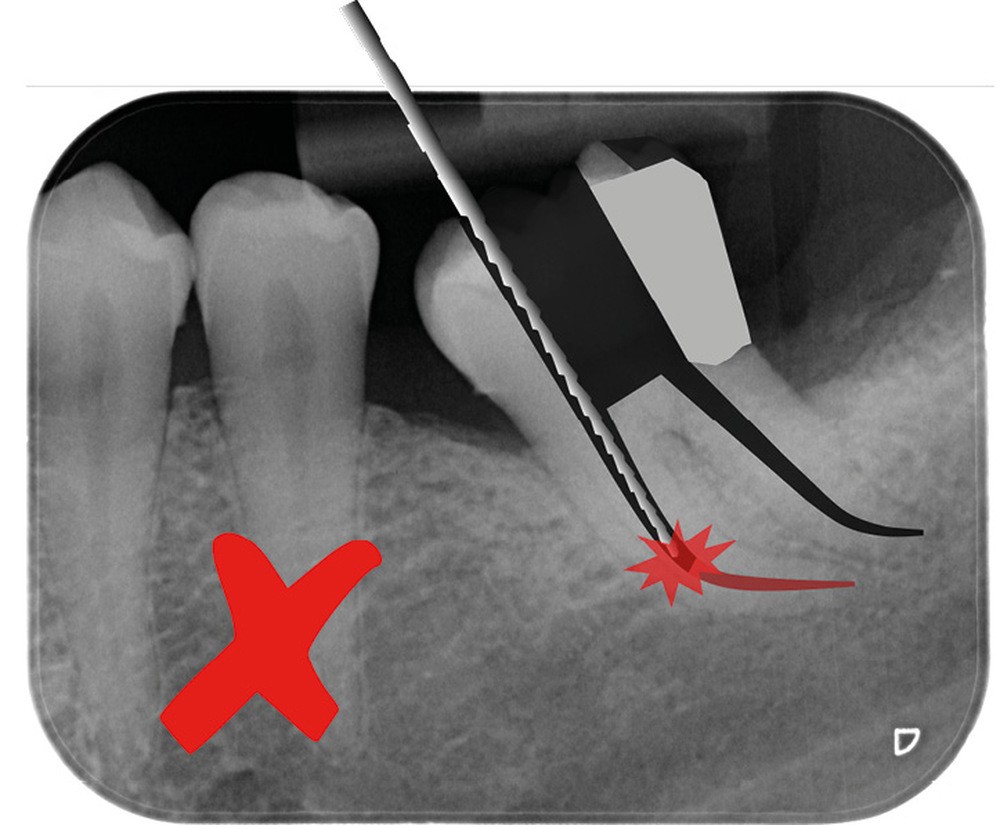

Trop petite

Une cavité d’accès trop petite [2] optimiserait le pronostic biomécanique (préservation dentaire maximale) mais pourrait compromettre le pronostic endodontique : mauvaise lecture de l’anatomie, instrumentation partielle, non ergonomique et avec risque de fracture, défaut de nettoyage des parois canalaires [3], irrigation inadéquate, difficulté d’obturation canalaire, voire d’obturation coronaire. Ce sera le cas des cavités d’accès « Ninja » [4] ou ultraconservatrice (fig. 1), des cavités d’accès « Truss » [5] (fig. 2), des cavités d’accès dites « opportunistes » [6] (fig. 3).